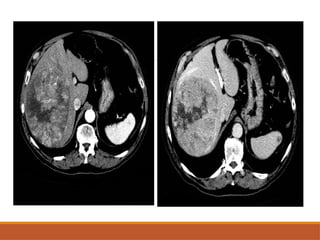

• #31 Axial cect images of hcc in segment 4a in showing enhancement odf elsion in arterial phase and washout of tumour in portal venous phase and delayed phases So early washout of the contrast suggestive of hcc

CT SCAN

NECT: large hypodense mass, often with central area of

low attenuation(necrosis).

May be isodense to liver.

CECT: non necrotic area enhances strongly in arterial

phase & early washout in subsequent phases.

Detection of venous invasion (portal,hepatic veins,IVC).